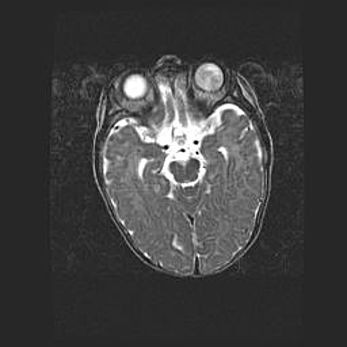

Множественные кисты обоих полушарий головного мозга, наибольшая из них в правой затылочной области. Ассиметричная атрофическая гидроцефалия.

Возраст: 7 месяцев

Вес: 5660 г

Пол: мужской

Окружность головы: 41,5 см

Срок гестации: 28-29 недель

Кисты головного мозга развиваются в результате многоочаговых некрозов вещества мозга и возникают вследствие перенесенной перинатальной инфекции, менингитов, энцефалитов, асфиксии, родовой травмы, расстройств мозгового кровообращения различного генеза. Образованию кист в веществе головного мозга плодов и новорожденных способствуют такие факторы, как высокое содержание в нем воды, недостаточная (или отсутствие) миелинизация и слабая астроглиальная реакция на повреждение.

Кисты могут сочетаться с гидроцефалией и другими поражениями головного мозга.